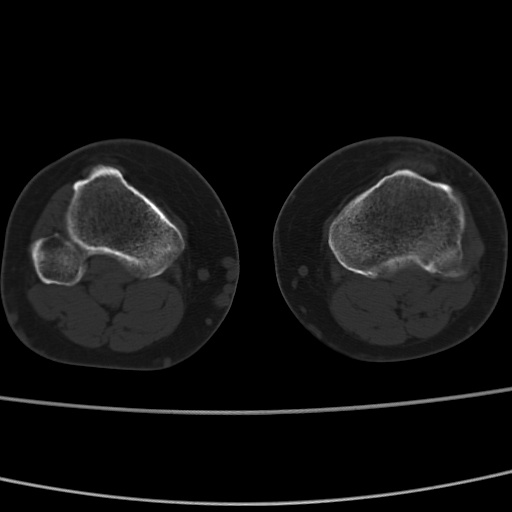

女性,50岁。【请提供患者临床症状体征】

胫骨后缘陈旧性骨折(是否有病史)

右膝关节退行性改变,关节游离鼠。

右膝关节退行性改变,滑膜黏液囊钙/骨化并游离。